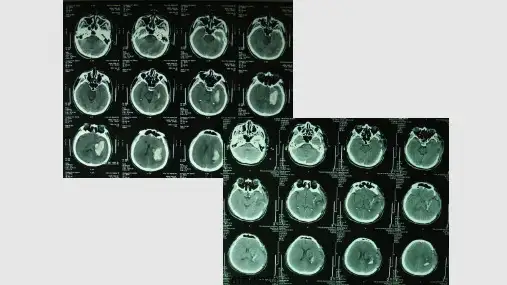

1.头颅CT

确诊脑出血的首选检查方法